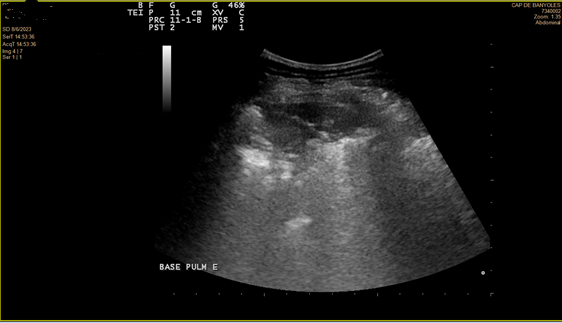

En la ecografía se objetiva irregularidad en la línea pleural, líneas B coalescentes (light beam) y un patrón de consolidación pulmonar en ambas bases pulmonares (I > D).